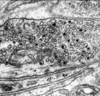

What is another term for neuronal cytoplasm?

What is another term for neuronal RER?

Perikaryon;

Nissl bodies